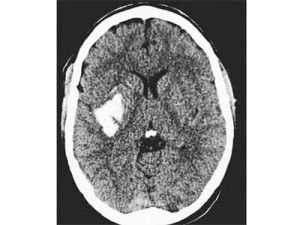

С точностью распознать геморрагический инсульт помогают информативные спиральная (СКТ) или мультиспиральная (МСКТ). Суть её заключается в послойных рентгеновских снимках головного мозга, на которых кровоизлияние достаточно хорошо видно см. рисунок.

кровоизлияние на КТ головного мозгаДругой метод, позволяющий диагностировать ГИ магнитно-резонансная томография или МРТ. Этот метод диагностики более точен, в сравнении с компьютерной томографией.